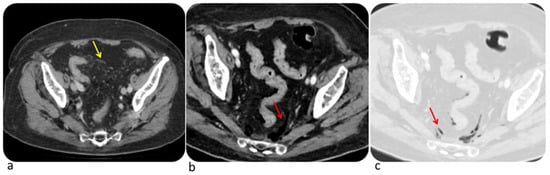

| Diffuse Colitis | Segmental Colitis |

|---|---|

|